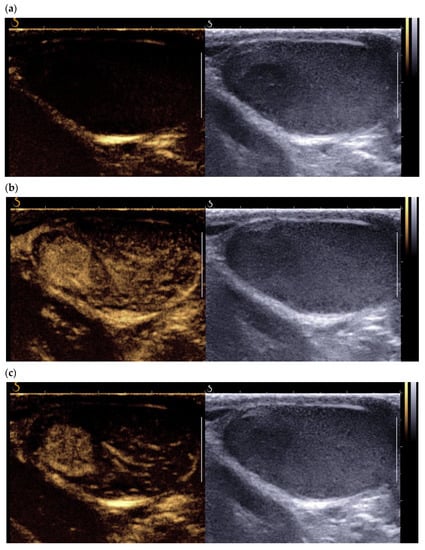

3.3. Contrast-Enhanced Ultrasound